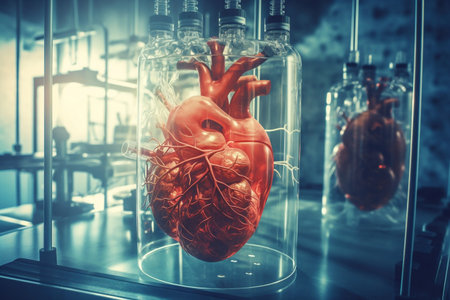

Human heart in a glass box on the table. 3d rendering